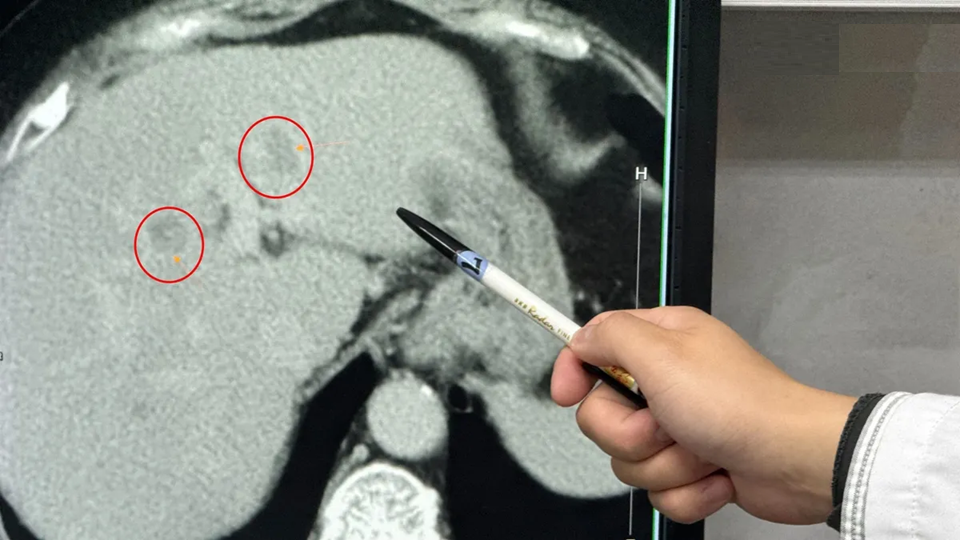

Theo bác sĩ Ngô Khôn Đạt, bác sĩ ngoại tổng quát đang công tác tại Bệnh viện Liên hợp Lý (Đài Loan, Trung Quốc), bệnh nhân nhập viện vì cảm thấy cơ thể mệt mỏi bất thường. Khi siêu âm ổ bụng tại khoa tiêu hóa, các bác sĩ phát hiện gan nhiễm mỡ mức độ nặng kèm theo nghi ngờ có khối u. Kết quả kiểm tra chuyên sâu cho thấy có hai khối u nằm ở thùy ngoài bên trái và phần giữa thùy trái của gan.

Đáng chú ý, tỷ lệ mỡ trong gan của bệnh nhân lên tới 40-60%. Bác sĩ cho biết, ngay cả với người trẻ có gan khỏe mạnh, khi phẫu thuật cắt gan cũng cần bảo tồn ít nhất 1/3 thể tích gan để duy trì chức năng sống. Trong trường hợp này, nếu cắt toàn bộ phần gan trái có khối u, nguy cơ suy gan sau mổ là rất lớn.